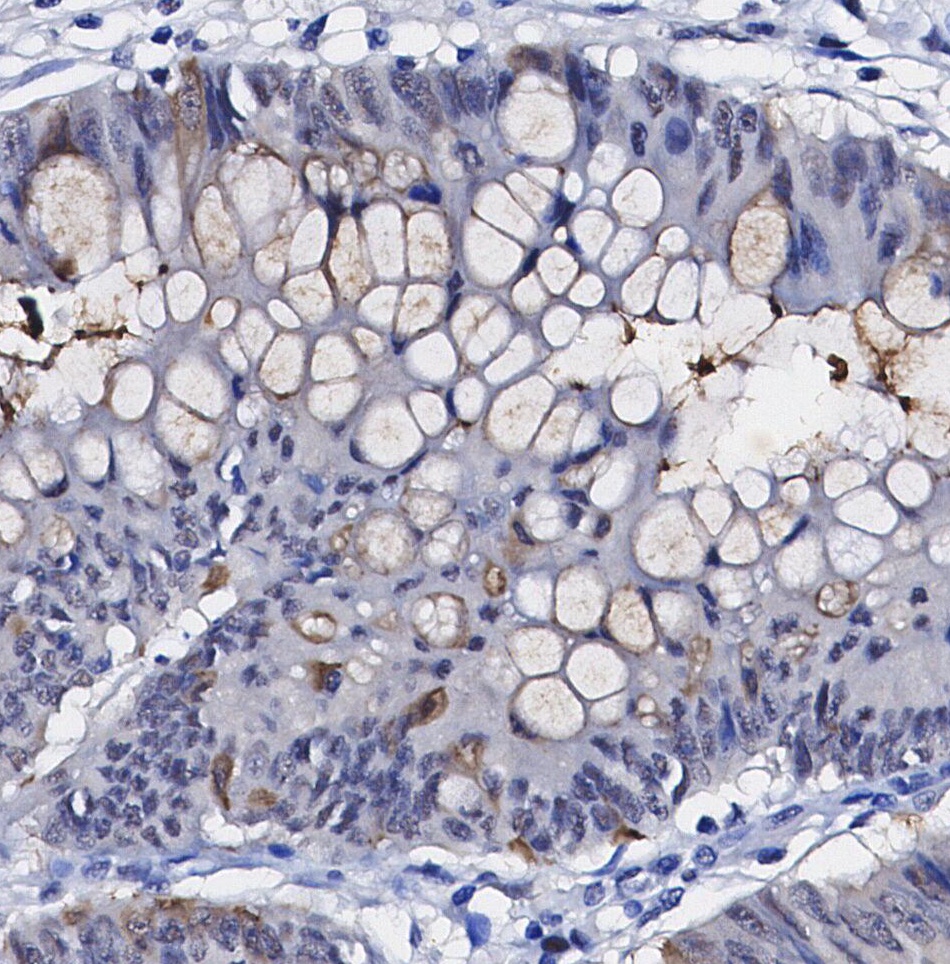

• Immunohistochemical analysis of formalin fixed paraffin embedded human Colorectal cancer tissue with F0528 at 1/100 dilution.